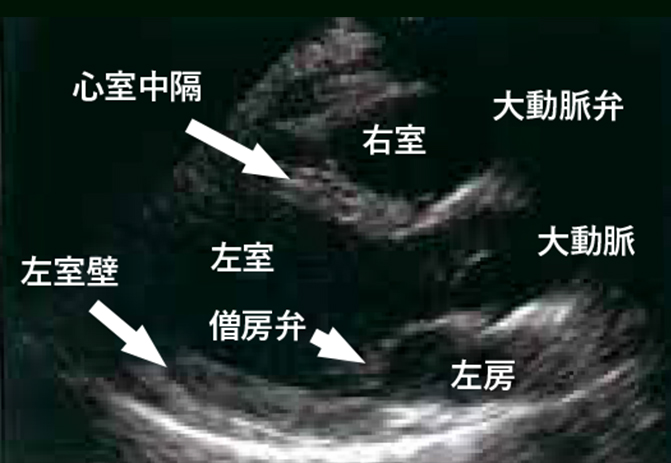

心臓超音波検査は心臓用の超音波装置を使用して、心臓の筋肉や弁の形態・大きさ・動きに異常がないかを見る検査です。

また、心臓内の血液の流れをカラーで表示することも可能で、血液の逆流や流量も見ることが可能です。

左室→左房への逆流が見受けられます